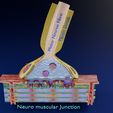

神经肌肉接头示意图